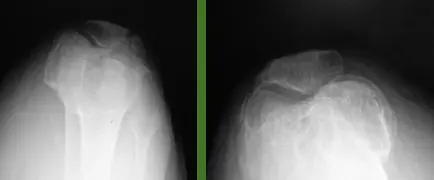

Case: Adhesive Capsulitis (Frozen Shoulder)

Clinical Scenario

- Patient: 55-year-old male, diabetic

Physical Examination Findings:

Q1: Describe the physical finding?

- The patient is unable to raise his right hand above his head

Q2: What is your differential diagnosis?

- Adhesive capsulitis (Frozen Shoulder) - Primary diagnosis

- Acromioclavicular arthritis

Q3: What is the treatment for such a case?

- Steroid injection

- Physiotherapy

- Arthroscopic release